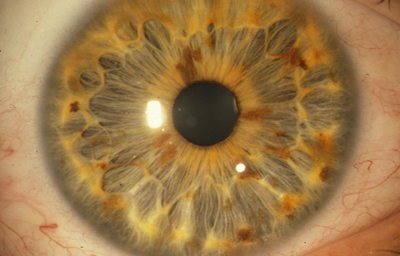

Alrededor del 7º mes la vascularización de la porción mesodérmica del Iris, (estroma iridiano) está llegando a su condición definitiva y el circulo vascular menor se reconoce; la túnica vasculosa lentis ya se ha atrofiado en sus porciones posterior y lateral, e inicia atrofia de su porción anterior (membrana pupilar) afectando en primer lugar su zona central; primero en las arcadas finales del centro los vasos se encogen, pierden circulación y quedan formando pequeñas espirales; el ectodermo iridiano con el esfínter ya se ha profundizado, está a nivel de las segundas arcadas vasculares de la membrana pupilar; cuando progresivamente la segunda arcada se atrofia, la membrana queda separada del margen pupilar y toma la apariencia de 2 capas: una anterior (la membrana pupilar) y otra posterior, el margen de la verdadera pupila. Esa grieta o seudoespacio tiene una extensión muy variable; por lo general, solo se ve en el borde de la pupila, pero puede ocurrir que comprometa la capa superficial de vasos periféricamente. Puede ocurrir que el proceso de atrofia no se detenga en la infancia y continue lentamente a lo largo de la vida, hasta que al final toda la hoja vascular anterior se separe del estroma profundo y quede flotando libre en la cámara anterior unida únicamente en la máxima periferia al estroma iridiano (Iridosquisis).

Lo que generalmente se ve, son parches de atrofia localizados periféricamente al margen pupilar, que toman la apariencia de criptas en el estroma.

El modelado final del Iris adulto, tendrá gran cantidad de variaciones dependientes de la cantidad de atrofia de su hoja anterior y de la pigmentación que desarrolle.

El desarrollo del pigmento en el Iris ocurre después del nacimiento y se define después de los 6 meses. Es de anotar que el esculpido del Iris que se aprecia en los adultos con ojos azules o grises, es debido a la visibilidad de las paredes de los vasos; en los iris muy pigmentados el detalle de la estructura queda oculto.